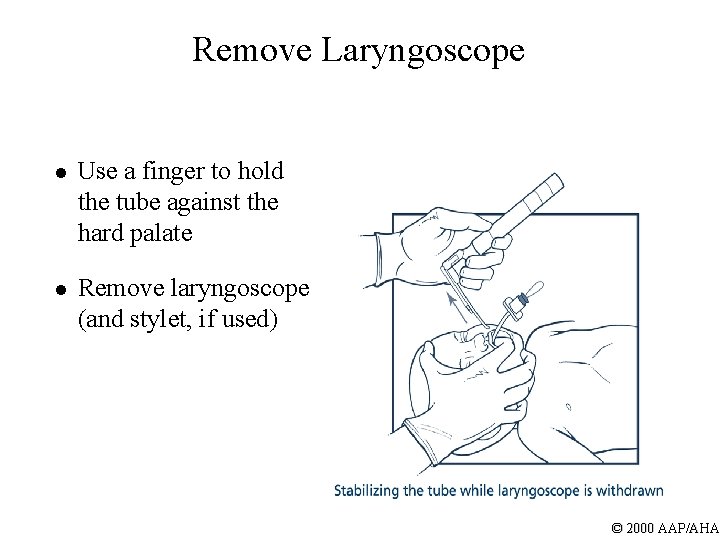

Remove Laryngoscope l Use a finger to hold the tube against the hard palate l Remove laryngoscope (and stylet, if used) © 2000 AAP/AHA